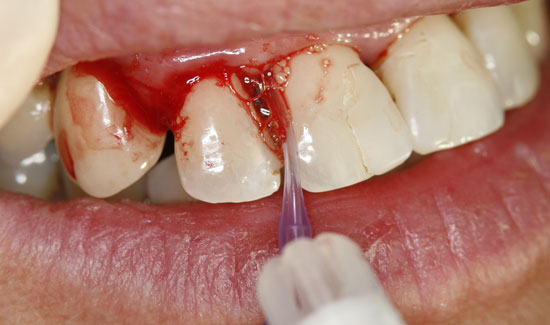

Abb. 2: Klinischer Aspekt der Regio 12, Entstehung von Gasblasen am entzündeten Gewebe. Fortlaufende Absaugung in der Nähe des Einsatzgebietes